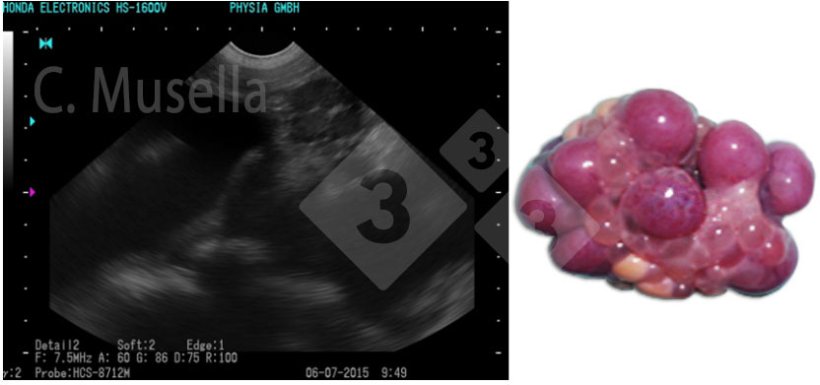

Die Diagnose einzelner oder mehrerer Ovarialzysten ist relativ einfach, auch wenn die vollständige Identifizierung der Zystenart anhand des Ultraschallbildes nicht immer sicher ist.

Abbildung 3: Polyzystische Ovarien